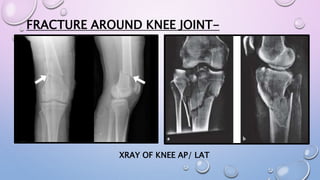

FRACTURE AROUND KNEE JOINT-

XRAY OF KNEE AP/ LAT

XRAY OF KNEE AP/ LAT/ SKYLINE VIEW

ABOVE KNEE SLAB

EXTEND FROM MIDDLE OF THE THIGH TO BASE OF TOES

KNEE IN 5-20* FLEXION

ANKLE IN NEUTRAL POSITION